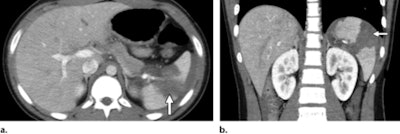

Biyyam's team listed the following injuries caused by handlebar trauma that can be diagnosed with CT and described some of the findings' characteristics.

- Abdominal: Pancreas, small bowel, mesentery, liver, spleen, adrenal gland (liver lacerations may present as linear hypoattenuating lesions; spleen lacerations range from linear to branching patterns)

- Pancreatic: Contusion and inflammation ("focal or diffuse enlargement of the pancreas with decreased enhancement and associated peripancreatic fat stranding and fluid")

- Duodenal: Hematomas (may visualize as "an intraluminal, intramural, or paraduodenal collection with increased attenuation"), perforations, lacerations ("interruption of the enhancing bowel wall, extravasation of intraluminal contents, or free retroperitoneal air")